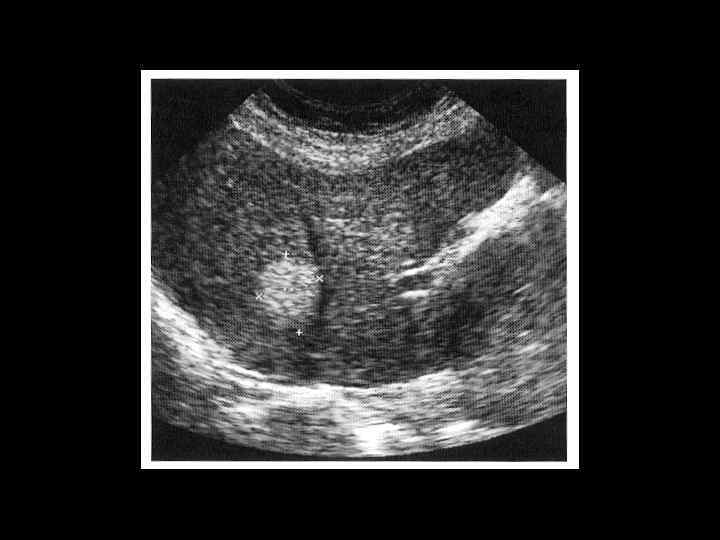

Пациент П. , 1945 г. р. С

Тот же пациент